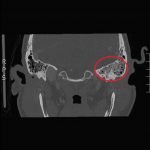

Significant findings:

The patient underwent computed tomography (CT) of the head which revealed opacification of the left middle ear (red arrow) and mastoid air cells (red circles). Additionally, there was thickening of the soft tissues of the external auditory canal (blue arrowhead), likely reflecting concurrent otitis externa.  Based on the imaging, he was admitted for findings consistent with acute otomastoiditis.